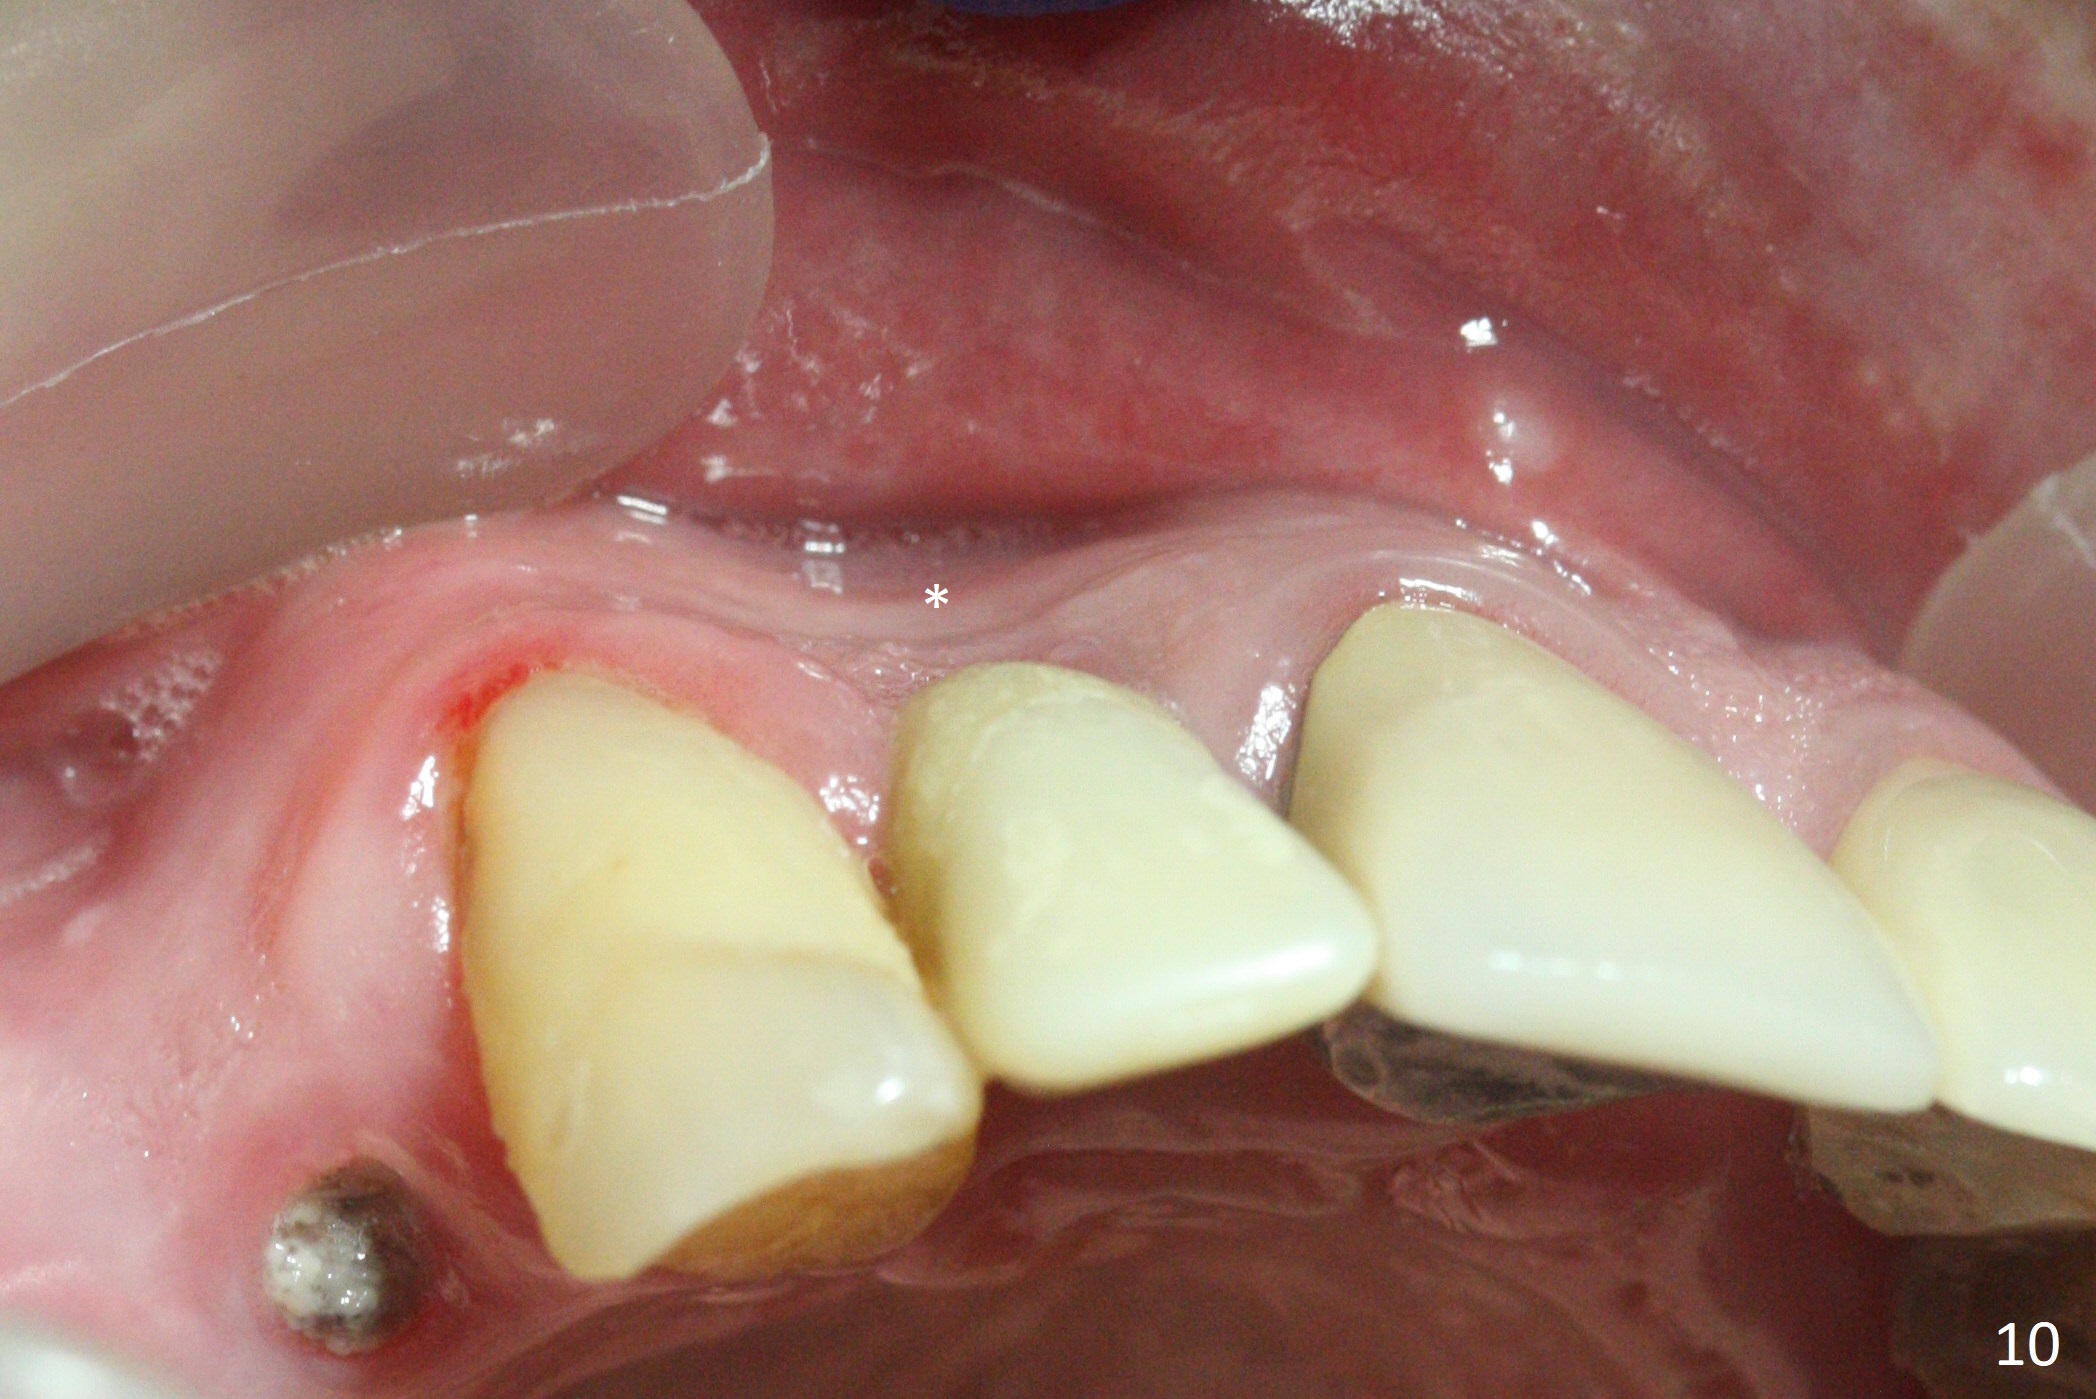

The residual root at #7 is fairly well exposed with buccal gingival recession (Fig.1). The implant placement is flapless (Fig.2-7). What is not shown is that the 3.8x13 mm implant is buccally subcrestally placed (Fig.3). After 1st round of bone graft buccal to the implant, a 4.5x5(5) mm abutment is immediately placed and prepared (Fig.4,5). An immediate provisional is placed after 2nd round of bone graft subgingivally buccally (Fig.6,7). Note the bulging gingiva (*), as compared to that in Fig.4,5. The long implant is chosen because of anterior deep bite (Fig.4) and lack of posterior support (Fig.7).

The gingiva adapts well to the provisional 1 week postop (Fig.8). The buccal gingiva remains recessive and the buccal plate is concave 5.5 months postop (Fig.9-11). It appears that the coronal portion of the buccal plate is resorbed 12 months postop (6 months post cementation, Fig.12 >). Socket shield or smaller diameter implant should have been done to avoid bone loss. Reanalysis of CBCT reveals that implantation apparently increases the bone width and that the buccal plate resorption is not so severe (Fig.13,14 (>: coronal end of the buccal plate)). Panoramic X-ray is taken 2 year 5 month post cementation.